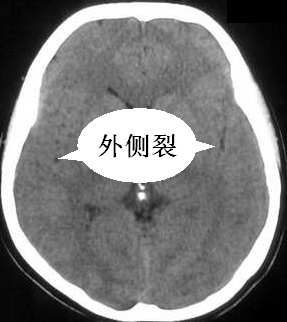

未见到右侧侧裂沟?可疑

我认为是正常的颅脑影像。左侧颞顶叶脑组织示略高密度结构是近外侧裂区的正常皮质结构,不是灰质移位。由于摆的位置不正,左侧的脑组织较右侧的低一个层面。